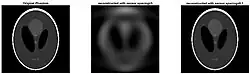

Deep learning methods are widely applied to image reconstruction nowadays and have achieved impressive results in various image reconstruction tasks, including low-dose denoising, sparse-view reconstruction, limited angle tomography and metal artifact reduction. An excellent overview can be found in the special issue [5] of IEEE Transaction on Medical Imaging. One group of deep learning reconstruction algorithms apply post-processing neural networks to achieve image-to-image reconstruction, where input images are reconstructed by conventional reconstruction methods. Artifact reduction using the U-Net in limited angle tomography is such an example application.[6] However, incorrect structures may occur in an image reconstructed by such a completely data-driven method,[7] as displayed in the figure. Therefore, integration of known operators into the architecture design of neural networks appears beneficial, as described in the concept of precision learning.[8] For example, direct image reconstruction from projection data can be learnt from the framework of filtered back-projection.[9] Another example is to build neural networks by unrolling iterative reconstruction algorithms.[10] Except for precision learning, using conventional reconstruction methods with deep learning reconstruction prior [11] is also an alternative approach to improve the image quality of deep learning reconstruction.